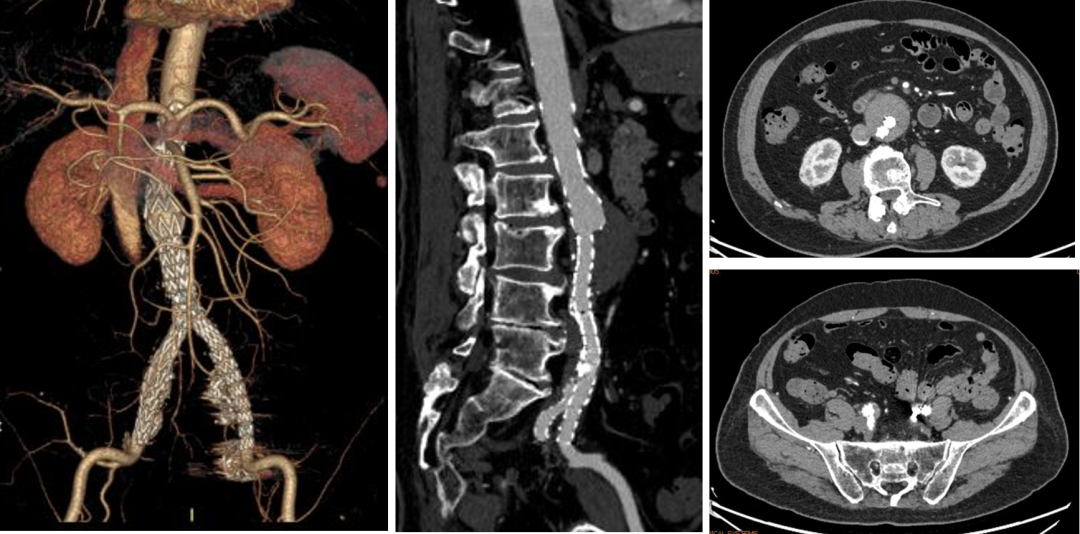

病情:患者男,71岁,双侧髂总动脉并左侧髂内动脉瘤,左侧髂总动脉起始部向右侧严重折曲,担心支架耐弯折性。

策略与操作:双侧差异化重建,右侧髂内动脉主干植入IBE支架;左侧髂内动脉壁支植入G-iliac™支架,通过右股入路配合可调弯导管超选至迂曲段。

右侧IBE,左侧IBD(经右股入路,可调弯导管与12F戈尔长鞘配合进入G-iliac及左侧髂内)

随访结果:术后2年CTA:左侧髂内动脉壁支支架通畅,折曲部位无狭窄或断裂,验证G-iliac™支架的柔顺性与耐久性。